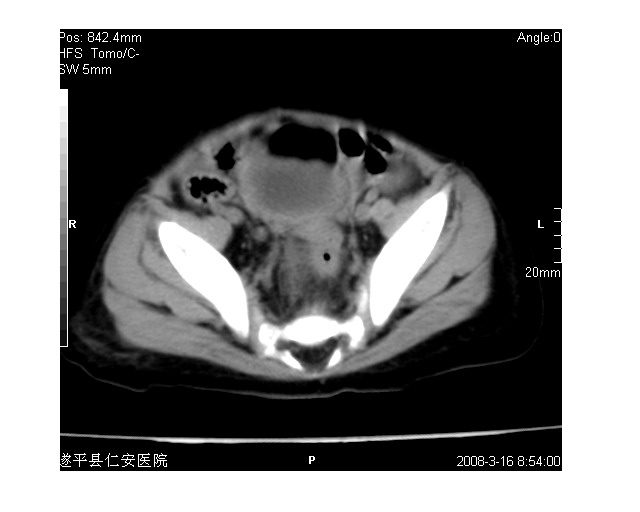

以下是引用lkc8963在2008-3-16 12:49:00的发言:[br]盆底巨大混杂密度肿块,富含多种组织成分包括脂肪/液体/软组织/钙化,边界清楚,向前压迫肠管及膀胱,向后突入骶尾部皮下脂肪层,首先考虑畸胎瘤,诊断时需要与脊柱裂/囊性淋巴管瘤等区别。